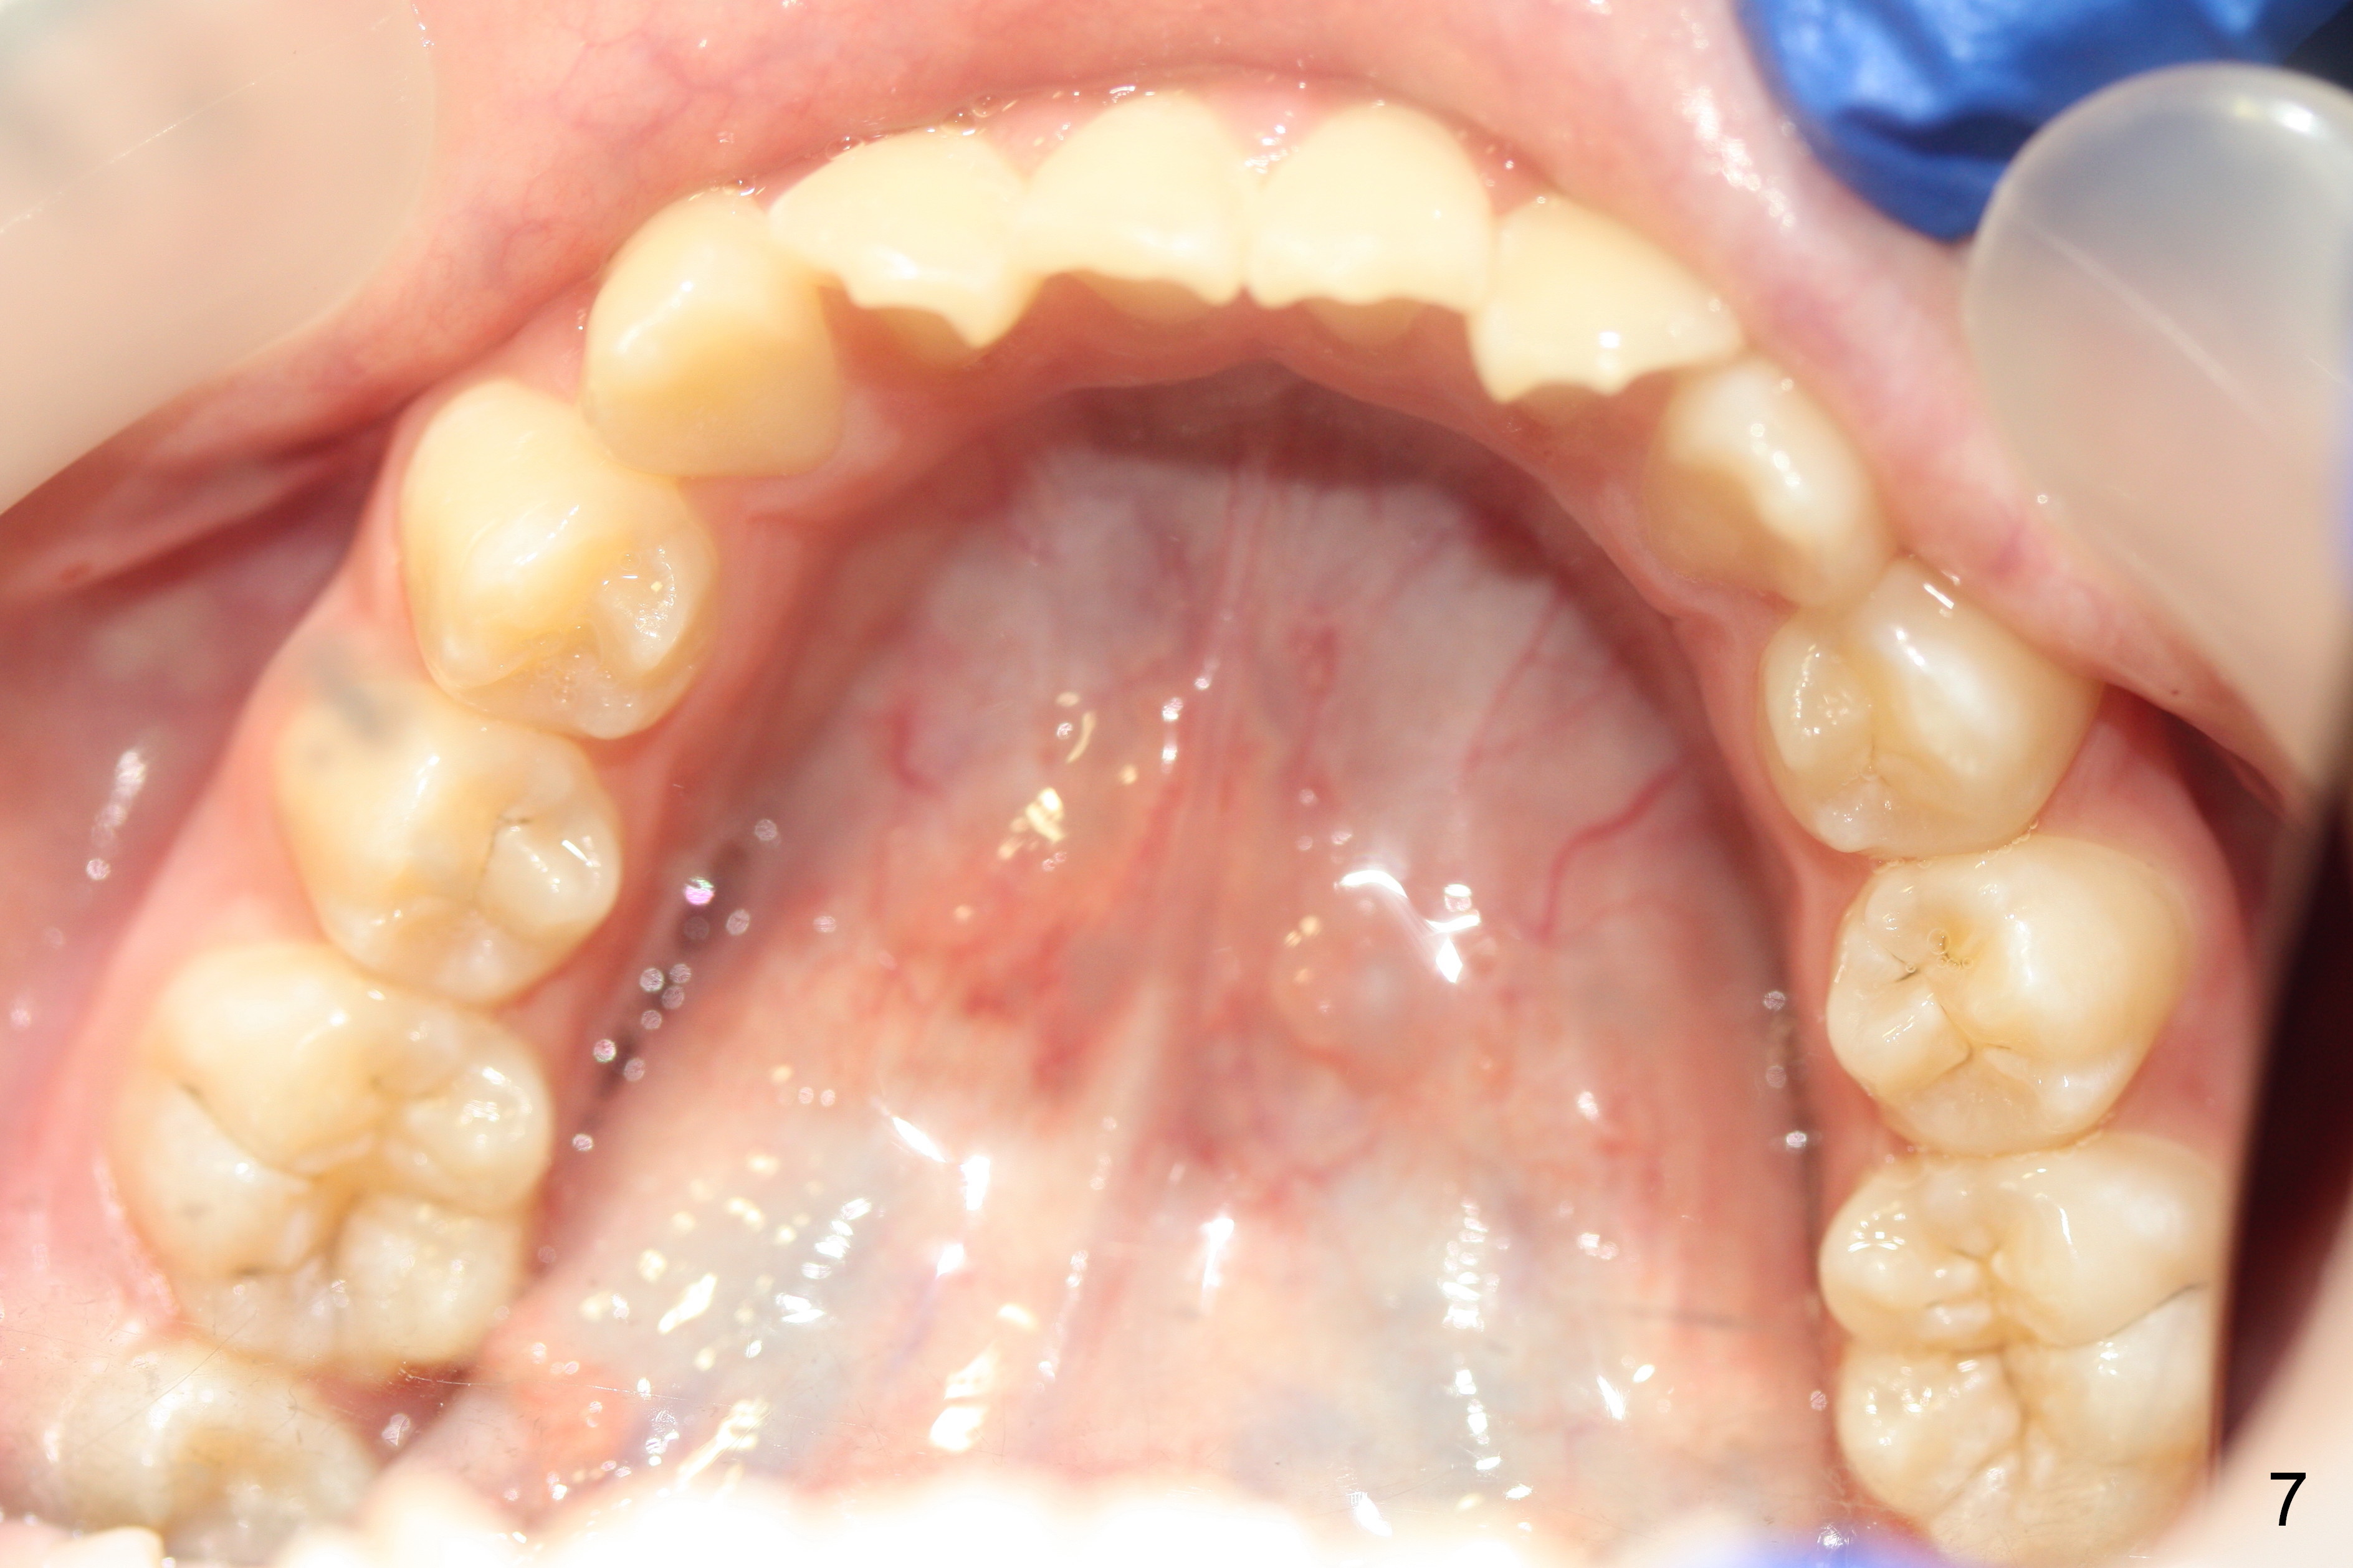

A 13-year-old girl presents for orthodontic consultation.  Chief complaint is crooked teeth.  Her brother is finishing 4 extraction ortho.

Looking at the records, the lower incisors are protrusive and have crowding, so think extraction.  There is enough combined crowding and class II to warrant extraction.  Since there is lower crowding, it would be 4 bicuspid extractions with the sliding mechanics using elastics or Niti closing coil springs. Closing the extraction space by maintaining the lower incisor position and moving the lower molars forward.  The upper arch is 50/50 front going back/back coming forward. Dr. Doug Ness, March 13, 2015 1:18 AM

We use brackets with increased lingual root torque to prevent lingual tipping of retracted incisors.

Closing with springs or rubber bands from 6s to hooks between the 2/3s.